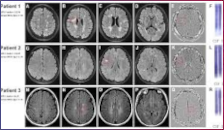

Le malattie infiammatorie demielinizzanti del sistema nervoso centrale (SNC) comprendono un gruppo eterogeneo di patologie con diverso decorso clinico (monofasico, recidivante e/o progressivo) e patogenesi immuno-mediata, di cui la più frequente è la Sclerosi Multipla (SM). La diagnosi di SM, in un paziente che ha avuto almeno una manifestazione clinica compatibile con evento demielinizzante del SNC, si basa su tre concetti …